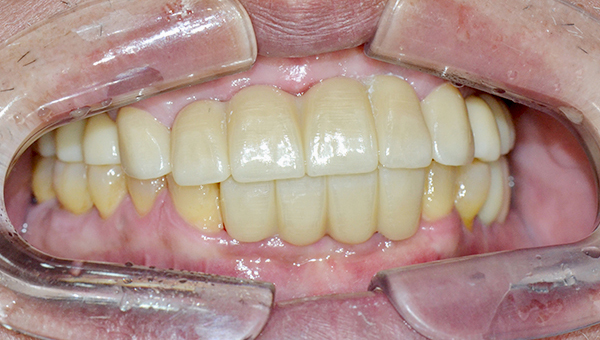

강*란 임플란트 시술 사례

전체 임플란트

2025.02.07

치료 전

2025.08.19

치료 후